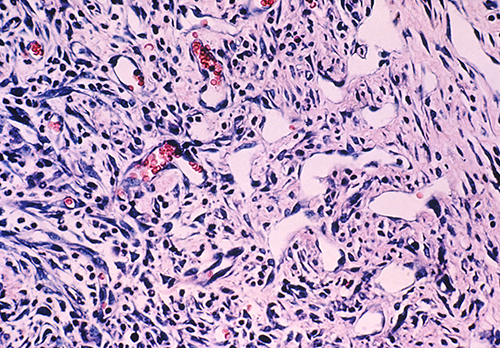

Virus-related cancers including cervical, anorectal and head and neck cancers associated with Human Papilloma Virus (HPV), Kaposi sarcoma and primary effusion lymphoma associated with Kaposi sarcoma-associated herpes virus, liver cancers associated with Hepatitis B and Hepatitis C viruses, and others are rapidly increasing in our region and disproportionately affect the African-American population. This increase may be explained in part by the large number of HIV+ patients in the region.